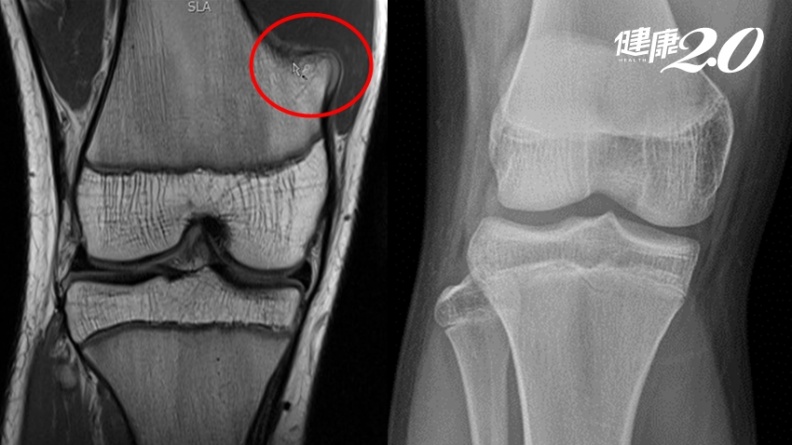

▲紅圈處為骨軟骨瘤,經過2年自行消失。

花蓮門諾醫院發表一例相當罕見的腫瘤消失個案。一名16歲的青少年,2年前右膝疼痛,檢查發現為3公分大的良性骨軟骨瘤,建議觀察追蹤即可;日前因打籃球引起雙側腳踝疼痛,再度回診追蹤,竟發現腫瘤消失不見,

收治個案的花蓮門諾醫院骨科主治醫師蔡傳恩指出,患者因腳踝疼痛回診,懷疑是骨軟骨瘤作祟,安排X光檢查發現,雙側腳踝並無明顯異常,且原本在右側遠端股骨的骨軟骨瘤竟然消失不見,讓本人及媽媽都非常高興,覺得真是太幸運了。